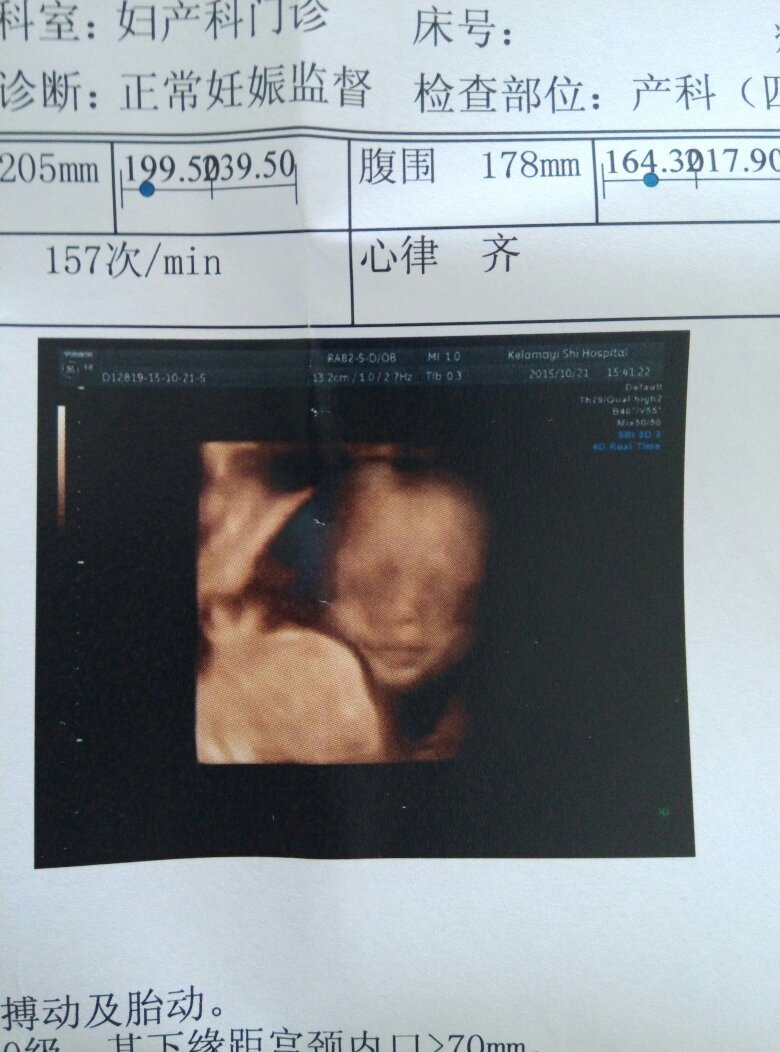

麻烦专家帮忙看一下我的四维彩超和唐筛报告有没有问题,四维图不清楚,老感觉宝宝嘴巴左上唇有阴影,鼻子也有阴影,不太放心,拍的时候医生也没说什么,但是还是担心,拜托了

超声图片和平时拍照片是不一样的。超声三维、四维成像是一种后期处理,今否大概方神貌法是把需要看胎儿部分和周围的羊水一起取样,再把羊水部分去掉,就剩下胎儿部分了,但是如局栋糕果在胎儿附近有其他结构,如胎盘脐带手脚等,机器就分辨不出来了,这样就感觉脸上或哪里长了什么东西,这个时候超声医生在动态观察的时候是可以分辨出来的,这也是超声和CT等检查不一样也是超声的优势——实时,动态。